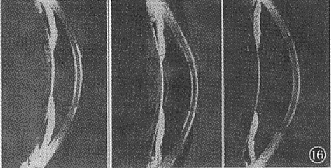

图16 瞳孔缘相对位置分级:+I位 (左图) : 瞳孔缘和晶状体前表面接触点相对虹膜根部附着点靠前,造成瞳孔阻滞,周边虹膜膨隆;0位 (中图) : 瞳孔缘和晶状体前表面接触点和虹膜根部附着点处于同一水平, 无虹膜膨隆征象;-1位 (右图) 瞳孔缘和晶状体前表面接触点位置相对虹膜附着点靠后, 周边虹膜呈反向性膨隆